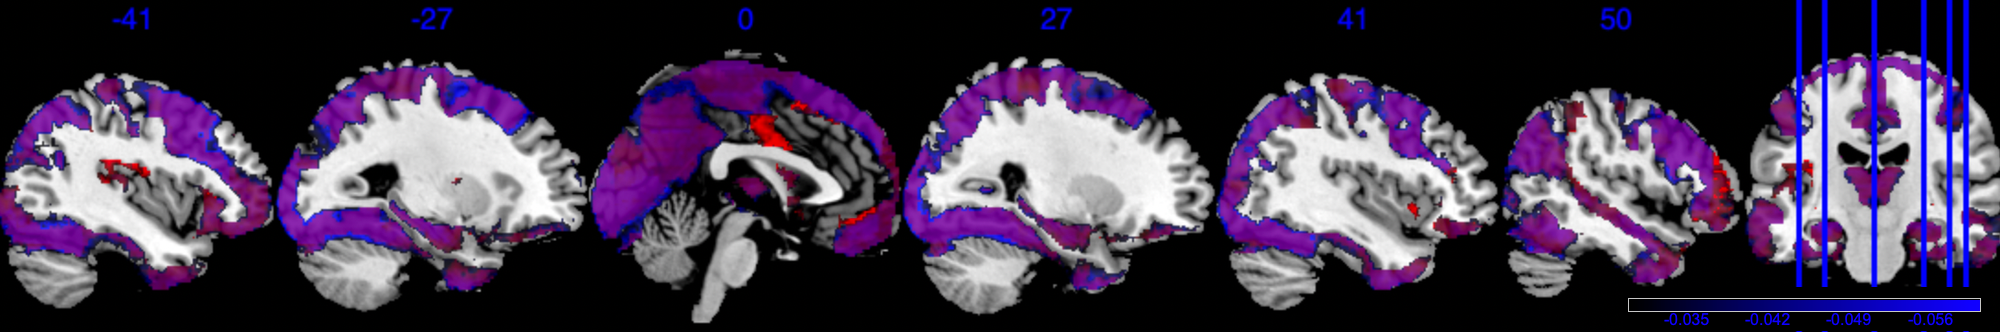

For a visual representation, Figure 3(a) shows the voxel level PIP in the sagittal plane. The highlighted red regions represent voxels with greater than 0.95 PIP. Figure 3(b) presents the effect size of , with the highlighted area in the range . Note that from Figure 3(b), voxels with PIP greater than 0.95 also correspond to voxels with a larger absolute value of effect size. We notice that the activation region (defined by voxel level PIP greater than 0.95) has a negative effect . This can also be validated by the scatter plot in Section D in the Supplementary Material, where the image intensity generally has a negative association with age across all individuals.

Based on our results, we have the following general interpretations: (i) when controlling for the confounders, age has a negative impact on the neural activity for emotion-related tasks; (ii) the negative effect reflected from each voxel is of very small scale, shown as in Figure 3(b), indicating a very low voxel level signal-to-noise ratio; (iii) the top 5 brain regions with the highest RLAR are (a) right intracalcarine cortex, right supracalcarine cortex, and left Temporal fusiform cortex, anterior division, all considered as critical areas for high-level visual processing including face recognition; (b) left temporal fusiform cortex, anterior division, a key structure for face perception, object recognition, and language processing (Weiner and Zilles, 2016); and (c) right inferior temporal gyrus, anterior division, an area for language and semantic memory processing, visual perception, and multimodal sensory integration (Onitsuka et al., 2004). These top 5 regions are also consistently identified in the sensitivity analysis when using half of the data as training data, see Section 4.4.1.

In addition, Figure 6 shows results equivalent to those in Figure 3, but with the selection indicator applied simultaneously to both the main effect and the interaction effect. As shown in Figure 6(b), the posterior of in model (10) is driven by both and . The regions exhibiting strong negative effects of do not fully align with the regions showing , in contrast to the original results in Figure 3(b). Therefore, if the primary interest is in the main exposure variable , such as age in our analysis, we recommend applying exclusively to this primary effect to achieve a more accurate selection of activation regions.

Since the gender variable is binary with female being 0 and male being 1, the interpretation for is that comparing to the female subjects, one standard deviation (s.d.) increase in age for male subjects is associated with -s.d. of change in the image intensity. The boxed green area in Figure 6(c) and Figure 6(b) identifies one active area where has a negligible effect, but has a large effect size, indicating that this area is associated with the differences of male’s age-brain intensity association compared to female. For example, one s.d. increase in male’s age is associated with at least 0.01 s.d. increase in brain signal intensity compared to the female baseline in this green-boxed area. On the other hand, Figure 6(d) also identifies areas where one s.d. increase in male’s age is associated with at least 0.01 s.d. decrease in brain signal intensity compared to the female baseline. The area in the green box spans several brain regions in the right hemisphere, including Right lateral occipital cortex, superior division, Right insular cortex, Right middle temporal gyrus, posterior division, and Right frontal operculum cortex. They jointly integrate information from multiple modalities and detect behaviorally relevant stimuli. The negative in Figure 6(d) spans over Right parahippocampal gyrus, posterior division, Right temporal fusiform cortex, posterior division, Left temporal fusiform cortex, posterior division, Left temporal pole. They jointly process and integrate vision and semantic information and are related to contextual and memory functions.